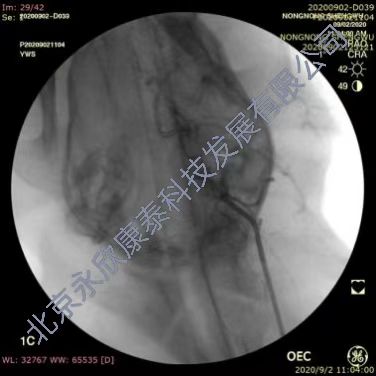

采用介入手术建立比格犬急性血栓性脑血管闭塞动物模型,分别于两侧腹股沟区备皮,消毒铺巾,穿刺右股动脉置入导管鞘,置入导丝,将5F单弯导管插至颈内动脉近端手推注显影剂确定血管走向,正侧位造影判断血管走行情况。用1mL注射器吸3~5条血栓条注入颈内动脉,造影证实颈内动脉颅内段末端栓塞,2h后造影复查血管的灌注情况,证实栓塞血管没有因血栓自溶复通,之后30min匀速脉滴注阿替普酶。溶栓治疗后1h,脑血管造影,判断血管复通情况,进行评分。